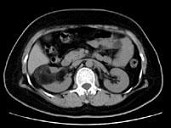

- 多项选择题男,55岁, 右腰部不适1年余,CT扫描如图所示, 下列说法正确的是 ( )

A、右肾中极可见一类圆形肿块影,肿块密度不均

B、其内见低密度脂肪影

C、其边缘清楚,与周围境界清晰

D、考虑为右肾癌

E、考虑为右肾错构瘤